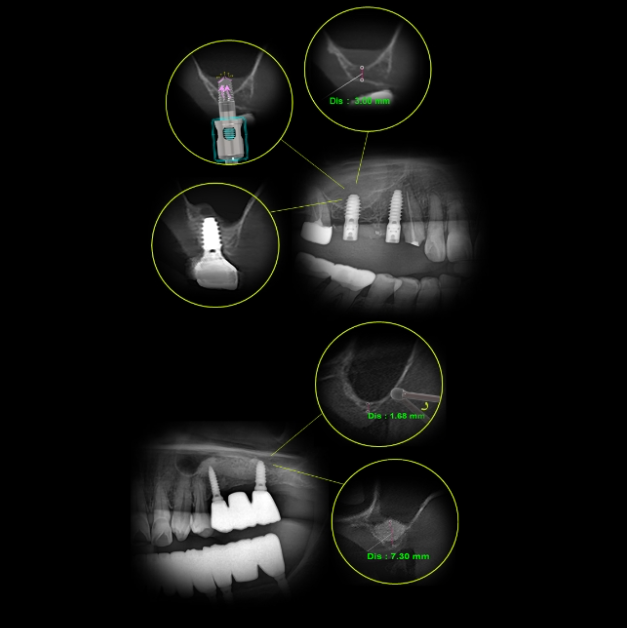

Concept 2DigitalDigital Minimalism

High Accuracy, increased efficiency- Accuracy

Leverage advanced digital diagnostics and guided workflows for precise implant planning and placement.

Minimize errors by focusing only on processing essential information and

at each step.